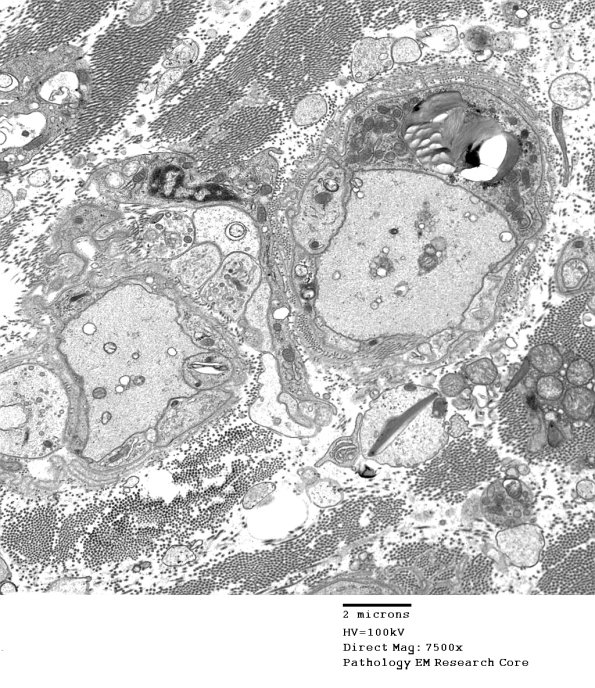

Two demyelinated axons. One axon shows adjacent cytoplasm of a Schwann cell which is mostly organelles and pi granules rather than engulfed myelin debris